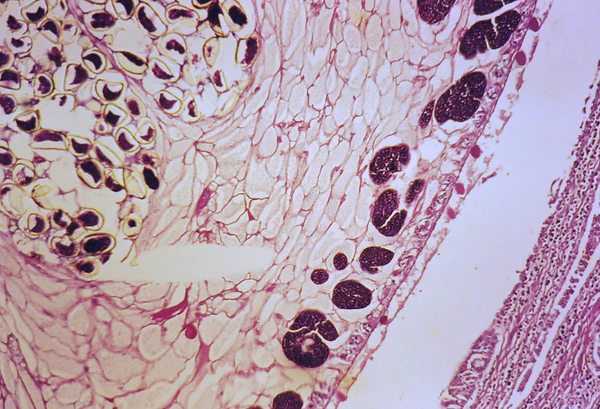

В основе патогенеза парагонимоза лежат воспаление и склероз ткани лёгких (иногда — других органов) под воздействием гельминтов. Сначала вокруг взрослых паразитов и их яиц развивается острая воспалительная реакция, при этом в инфильтрате преобладают эозинофилы. В дальнейшем вокруг очага формируется фиброзная капсула. Кисты, расположенные в лёгочной паренхиме, прорываются в бронхиолы. Их содержимое представлено кровью, яйцами гельминтов и воспалительным экссудатом. Если киста расположена субплеврально, может сформироваться эмпиема плевры, содержащая большое количество эозинофилов. Со временем в очагах поражения усиливаются склеротические процессы, а воспаление стихает. Некоторые очаги обызвествляются.

Диагноз лёгочного парагонимоза устанавливают на основании клинической картины, обнаружения яиц гельминта в мокроте, иногда и в фекалиях. Диагноз личиночного парогонимоза подтверждается серологическими реакциями со специфическим антигеном. При заражении P. szechuanensis диагноз устанавливают на основании результатов биопсии узла. В биоптате обнаруживают личинки паразита.